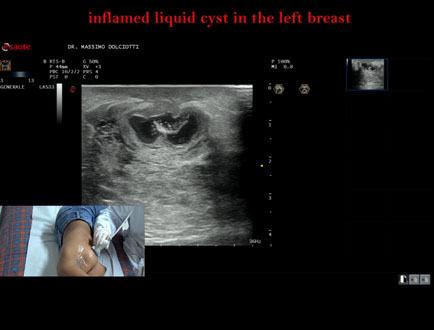

Data inserimento: 07/10/2025

Ecografia del: 15/05/2025

Strumento: Esaote MyLab Eight

Sonda: Lineare Multifrequenza 3-13 MHz

Età Paziente: F 16 anni

Motivazione dell'esame: da 2 giorni dolore alla mammella sinistra.

Commento all'esame: le immagini ed il video documentano al quadrante inferiore esterno ore 4 della mammella sinistra, formazione disomogenea ipoanecogena, delle dimensioni di 24 x 14 mm, da ricondurre a cisti liquida infiammata.

Conclusioni: cisti liquida flogosata alla mammella sinistra (inflamed liquid cyst in the left breast).

Presentazione: Dr. Massimo Dolciotti - Ancona